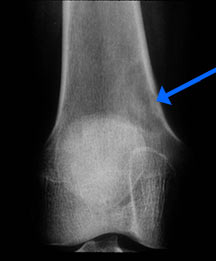

- May arise from any bone and any site within a bone (epiphyseal, metaphyseal, diaphyseal)

- Radiographically variable appearance: may appear benign (geographic) or malignant (permeative or moth eaten)